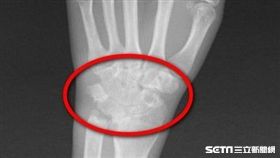

類風溼性關節炎

她認真教鋼琴 竟導致右手3條肌腱斷

31歲的鋼琴老師許小姐,有類風溼性關節炎病史,近2年...

2018/10/03 10:15

類風溼性關節炎發作 婦人見樓梯就怕

手腳關節腫脹 上下樓梯舉步維艱 58歲的邱女士是類...

2018/02/21 15:16